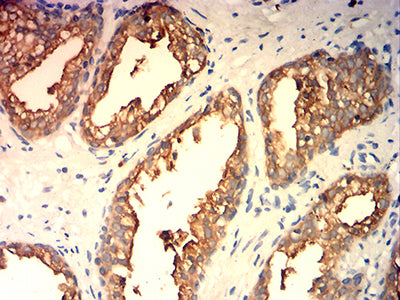

分类: 科研抗体货号: 32254别名: HO-1; HSP32; HMOX1D; bK286B10应用: IHC,FCM反应种属: Human